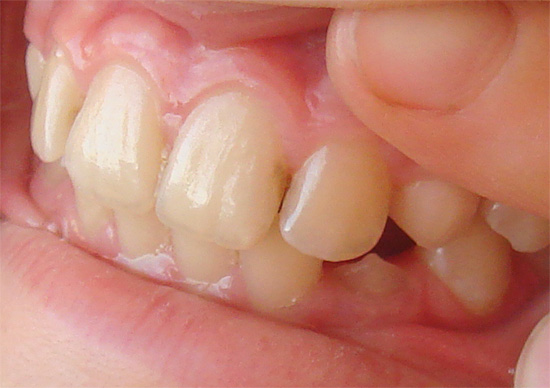

Carie nelle aree più vulnerabili dei denti - nell'area della fessura

Ci sono momenti in cui la diagnosi visiva non è sufficiente. Ad esempio, le aree interessate situate sulla parete dei denti nei punti del loro contatto non sono sempre visibili. A volte il processo cariato si sviluppa sotto vecchie otturazioni e corone, sotto la gomma (carie radicolari) e non puoi vederlo ad occhio nudo. Qui, i metodi diagnostici più accurati vengono in aiuto del dentista.